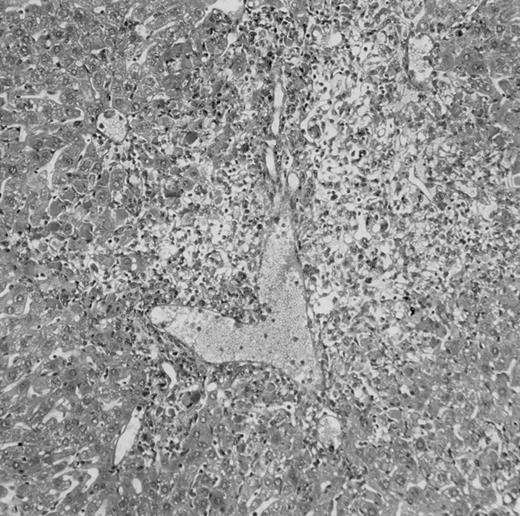

Histologic findings. Organs were collected at different times after BMT and tissue sections were stained with hematoxylin and eosin. Original magnifications for spleen (left) and liver (right) are ×40 and ×100, respectively. (A) B6 mice receiving FVB BM plus EpTK T cells. (B) Control group receiving BM only.

(C) B6 mice receiving FVB BM plus EpΔTK T cells and treated with GCV. (D) B6 mice receiving FVB BM plus EpΔTK T cells, treated with GCV, and developing a late onset GVHD (day 54).

On the other hand, 5 of 19 mice exhibited signs suggesting the occurrence of a delayed GVHD (Table 1). Clinically, these animals presented weight loss and/or skin lesions on ears, neck, limbs, or abdomen, but only after day 40. In the absence of any further GCV treatment, 2 mice died 14 and 29 days after the occurrence of these signs (Table 1A) with histological signs of severe GVHD (Fig 4D). These results suggest that, in these mice, the 7-day GCV treatment was sufficient to prevent early, but not delayed GVHD.